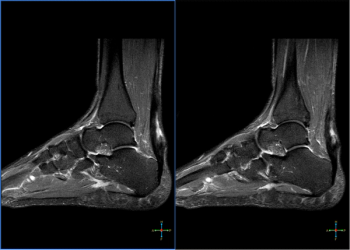

Patient presents with an Achilles tendon tear.